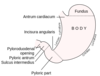

Where does the Upper GI tract end?

Duodenum